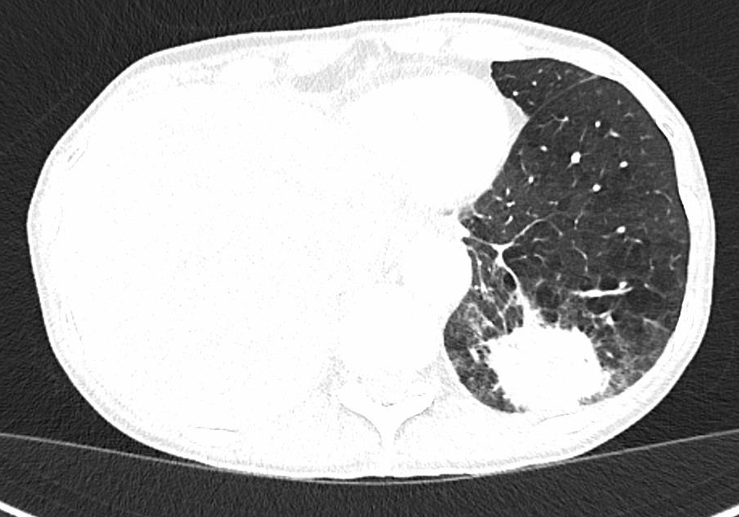

患者为一名63岁的女性,吸烟史长达30包年,无其他显著病史。主诉为不明原因的皮疹,既往未接受过系统性治疗。胸部CT和PET检查显示可疑的代谢性肺部肿块,伴同侧纵隔淋巴结转移。为进一步明确诊断,患者接受了EBUS活检,病理结果显示为肺腺癌,病理分期为N2。基因检测未发现常见驱动基因突变(如EGFR、ALK等),而PD-L1 TPS高达90%。根据AJCC/UICC第8版TNM分期,该患者被诊断为IIIB期(cT3N2M0)肺腺癌。基于患者较高的PD-L1表达水平及分期特点,临床团队决定采用新辅助治疗策略,以期改善手术切除率和长期预后。患者接受2周期的卡铂、紫杉醇和纳武利尤单抗联合治疗。然而,在治疗过程中,患者出现严重的免疫相关不良事件,包括4级肝炎和肺炎,迫使治疗中断。为控制irAE,患者接受大剂量皮质类固醇(甲泼尼龙1mg/kg)联合霉酚酸酯的免疫抑制治疗,症状逐渐缓解。治疗中断后,患者接受中叶切除术,病理结果显示完全病理缓解(pCR),未发现存活的肿瘤细胞,仅见纤维炎性肿瘤退缩和坏死区域。这一结果表明,尽管治疗过程中出现严重的irAE,但新辅助免疫治疗仍取得了显著的抗肿瘤效果。

术后随访期间,患者接受全身CT扫描,发现新的可疑肿瘤肿块,脑部CT显示可疑脑转移。这一发现引发复发的初步怀疑,但鉴别诊断需综合考虑其他可能性,包括新的原发肿瘤(如小细胞肺癌)或感染性疾病。为进一步明确诊断,患者接受肺细针穿刺活检,结果显示非坏死性肉芽肿和多核巨细胞,提示结核感染。患者随后接受标准抗结核治疗,病灶完全消退,目前无疾病复发迹象,随访仍在持续进行中。